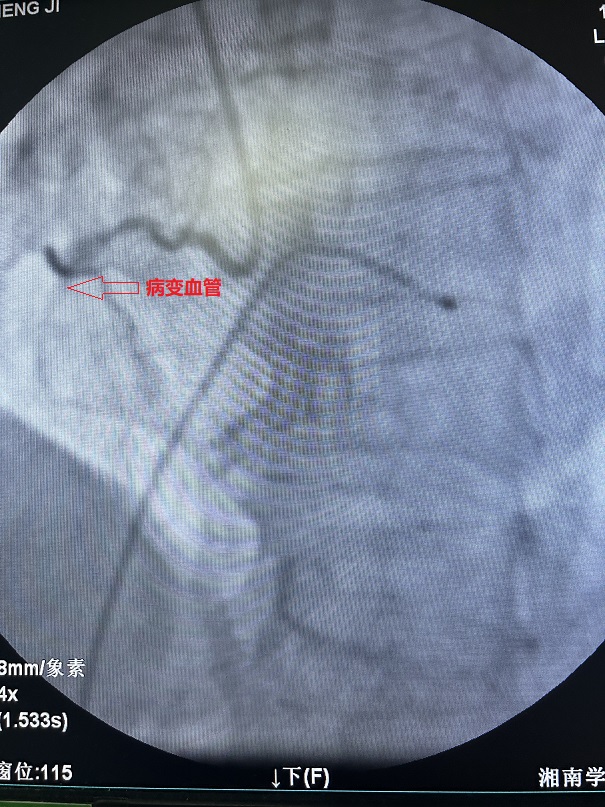

76岁的王先生,因反复胸闷5月余,加重伴气促2天入住心血管内一科。该患者数月前因突发急性心肌梗塞急诊行冠脉支架置入术,此次入院的主要目的是为了处理另一条严重狭窄并伴严重钙化的病变血管。

血管钙化病变素来是介入医生颇感头痛的“硬骨头”,常规的球囊、支架扩张技术难以充分扩张病变部位,一直以来被业界称为冠脉介入领域“最坚固的堡垒”。术前,心血管内一科廖昆团队为王先生充分评估了手术方案,根据患者实际病情,决定为他行冠脉内斑块旋磨术等血运重建术。

凭借精湛的技术和充分的准备,王先生的病变血管,在术中得以顺利开通并成功置入支架,术后患者胸闷气促症状得到明显缓解。王先生及家人都对治疗效果非常满意。